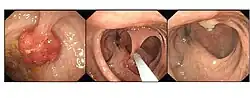

Polypectomy

Endoscopic polypectomy has been carried out since the early 1970s by both endoscopic snare removal and fulguration of polyps with hot biopsy forceps.[15][16]